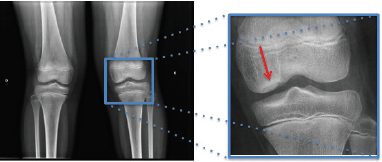

Considere a seguinte radiografia e assinale a alternativa que apresenta o diagnóstico mais provável.